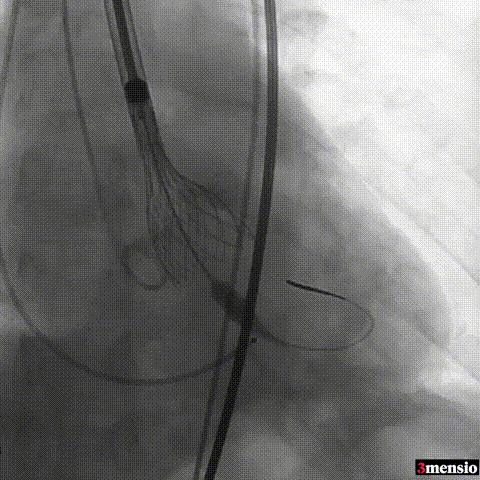

手术过程概览:

图片

主动脉根部造影

导丝跨瓣